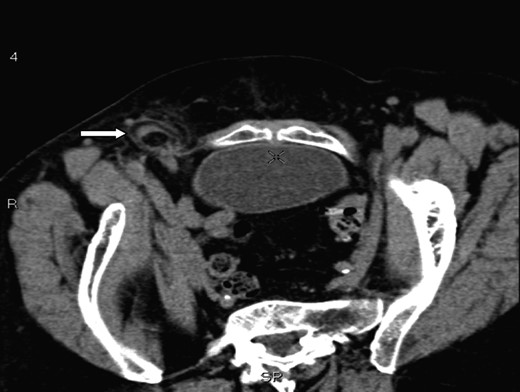

A 70-year-old female was referred by her general practitioner to our radiology department after presenting with a painless right groin swelling. An ultrasound scan showed a lymph node in the right groin with surrounding fluid and unusual appearances not typical of a hernia. A limited CT scan was subsequently performed which revealed a right femoral hernia containing the tip of the vermiform appendix with surrounding inflammatory change and an associated enlarged lymph node in keeping with a De Garengeot's hernia (Figs 1–3). On questioning, the patient first noticed the lump 2 weeks prior to presentation and said that it has gradually increased in size. It was not painful and she had no obstructive symptoms. Her medical history included COPD, breast cancer and a past history of tuberculosis.

A coronal section showing the tip of the appendix (white arrow) protruding through the femoral canal, medial to femoral vein (red arrow) into the hernia. The appendix measures 10 cm.